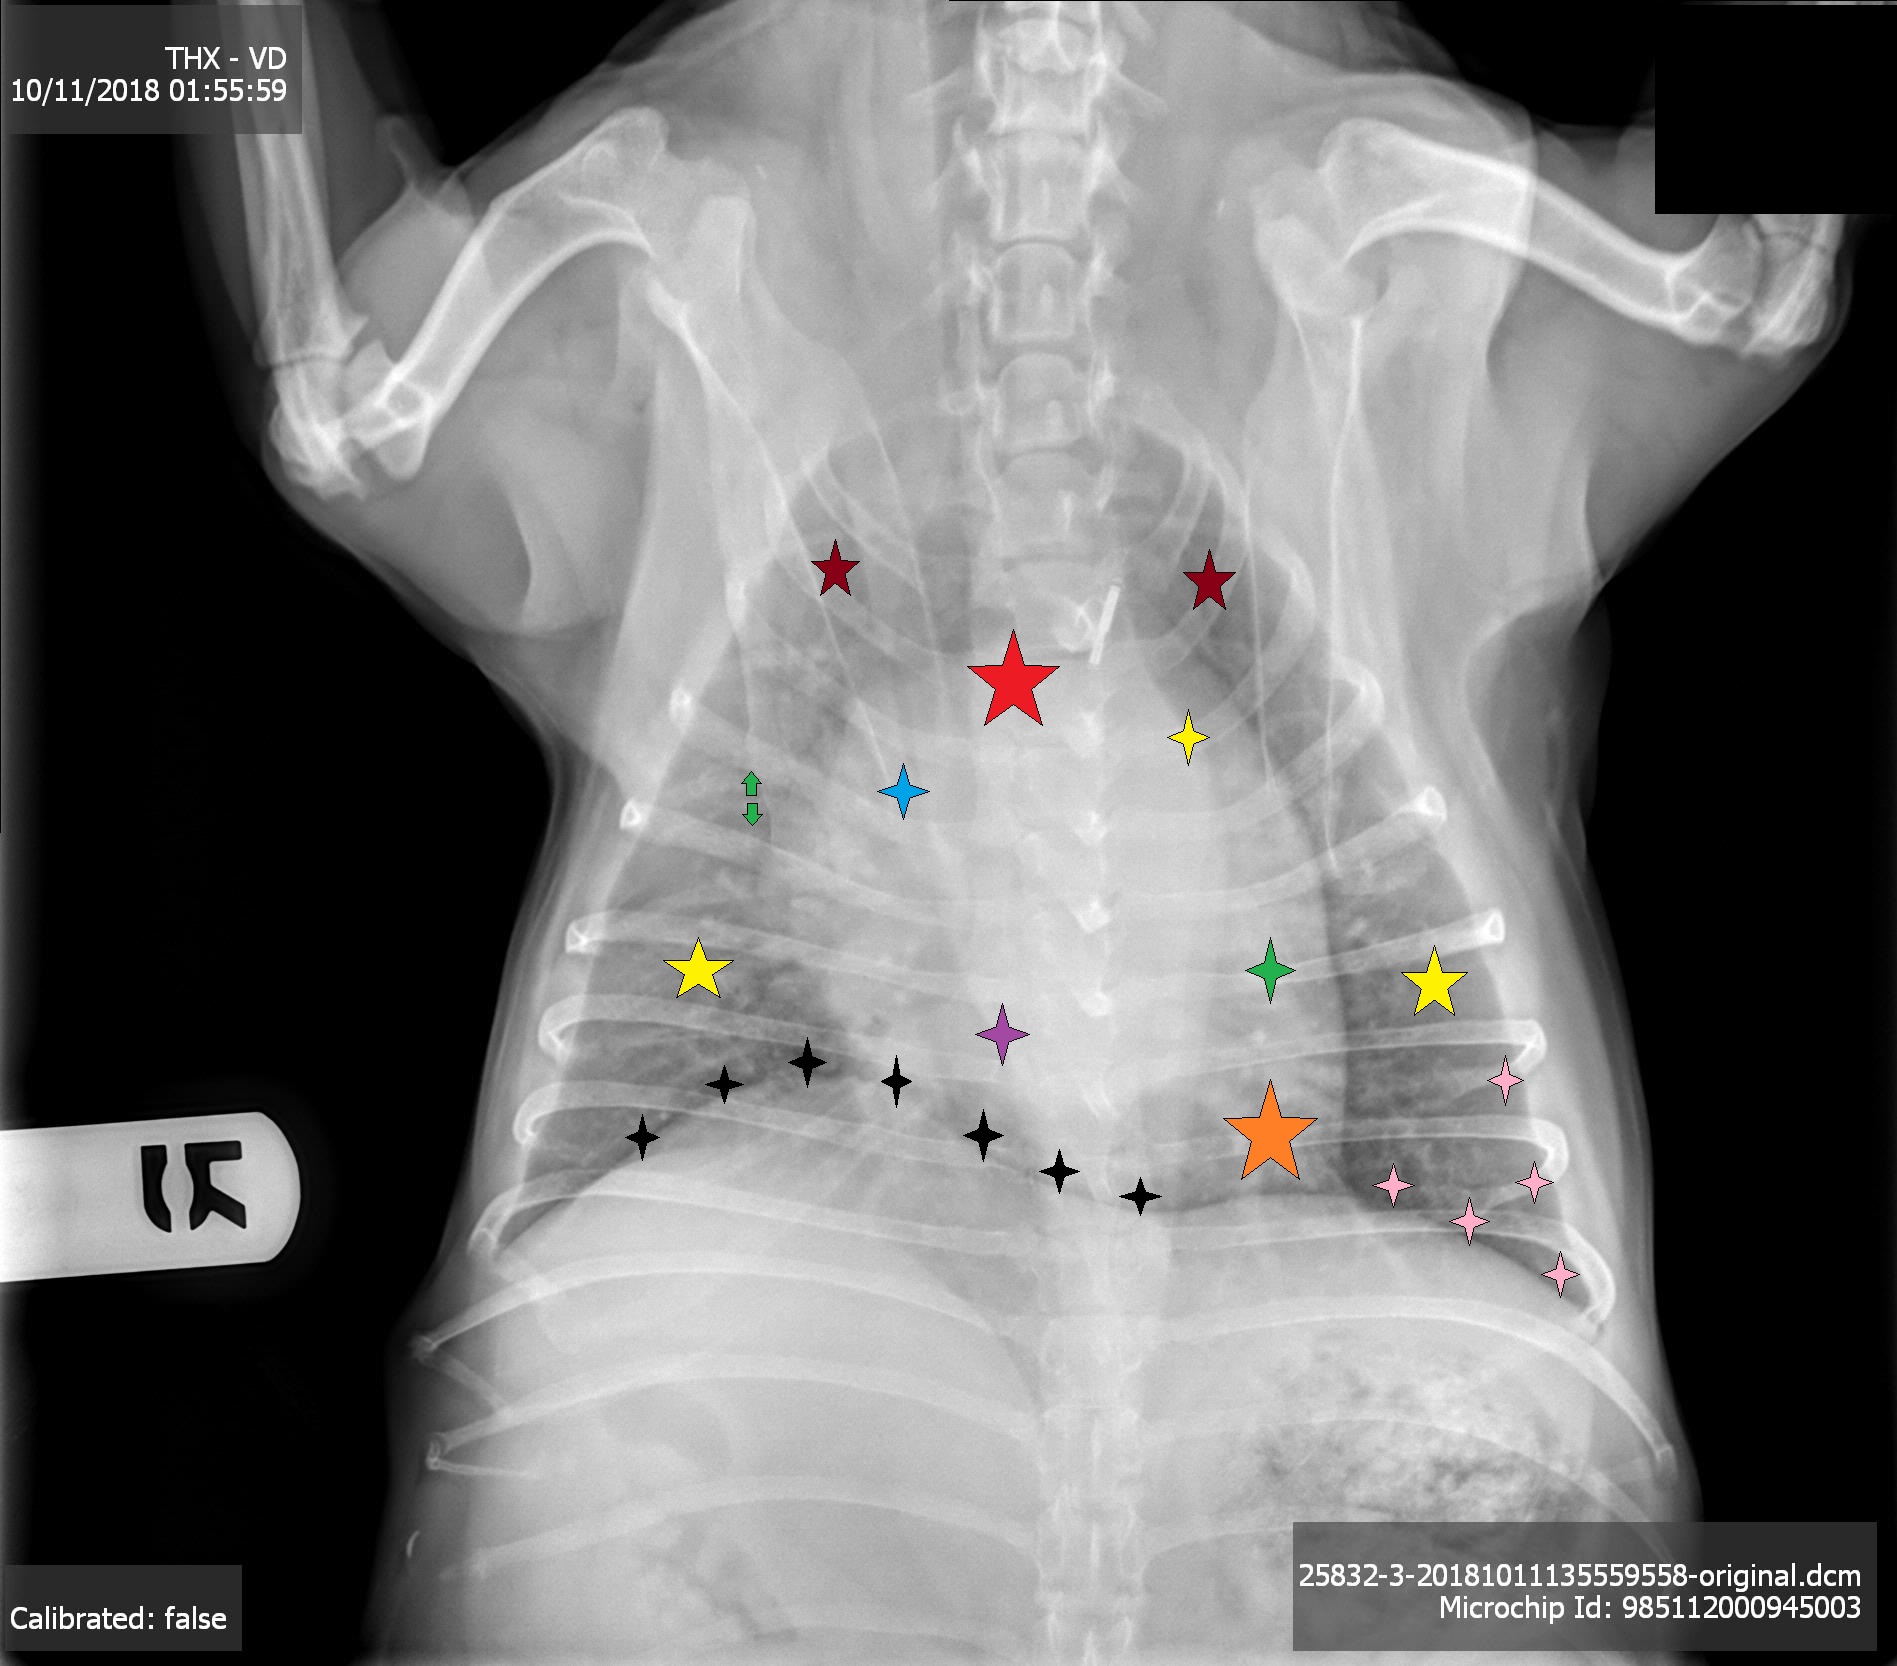

Maroon Stars

Cranial Lung Fields

Red Star

base of heart

Blue Asterisk

Right atrium

Yellow Asterisk

Left atrium

Purple asterisk

right ventricle

Green asterisk

left ventricle

orange star

apex of the heart

Yellow stars

caudal lung fields

pink asterisks

left crus

black asterisk

Diaphragm